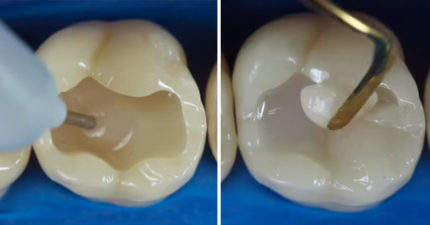

影/牙醫讓人想到都怕 「用俯瞰視角看補牙過程」其實療癒到爆!